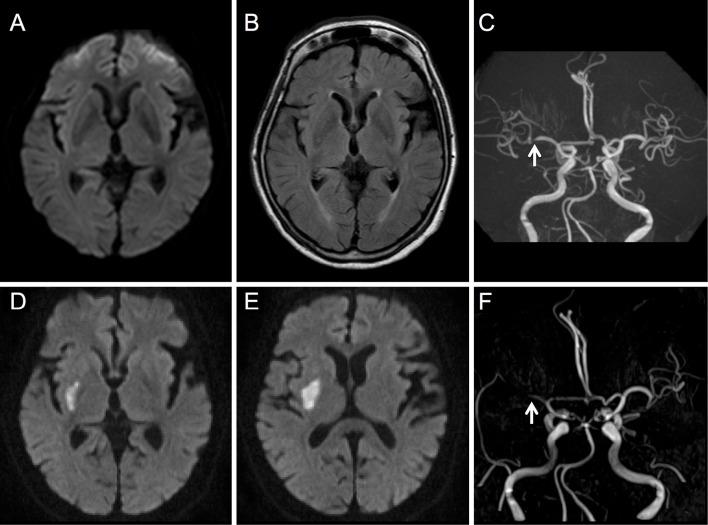

We herein report an 84-year-old woman with right middle cerebral artery (MCA) stenosis who presented with persistent left hemichorea preceding cerebral infarction. She visited our hospital on day 9 after the hemichorea onset. Magnetic resonance imaging (MRI) showed no acute cerebral infarction. Magnetic resonance angiography revealed right MCA stenosis. Her hemichorea persisted for 19 days and subsequently disappeared. On day 21, she developed left hemiplegia. Repeat MRI revealed a cerebral infarction in the right putamen. MCA stenosis can present with persistent hemichorea, even in the absence of cerebral infarction. Persistent hemichorea with MCA stenosis may presage cerebral infarction.

我们在此报告一例右侧大脑中动脉(MCA)狭窄的 84 岁女性患者,其在脑梗死前出现持续的左侧偏侧舞蹈症。她在偏侧舞蹈症发作后第 9 天就诊于我院。磁共振成像(MRI)未见急性脑梗死。磁共振血管造影显示右侧 MCA 狭窄。她的偏侧舞蹈症持续了 19 天,随后消失。第 21 天,她出现左侧偏瘫。重复 MRI 显示右侧壳核脑梗死。MCA 狭窄可表现为持续的偏侧舞蹈症,甚至在没有脑梗死的情况下也是如此。伴有 MCA 狭窄的持续偏侧舞蹈症可能预示着脑梗死。